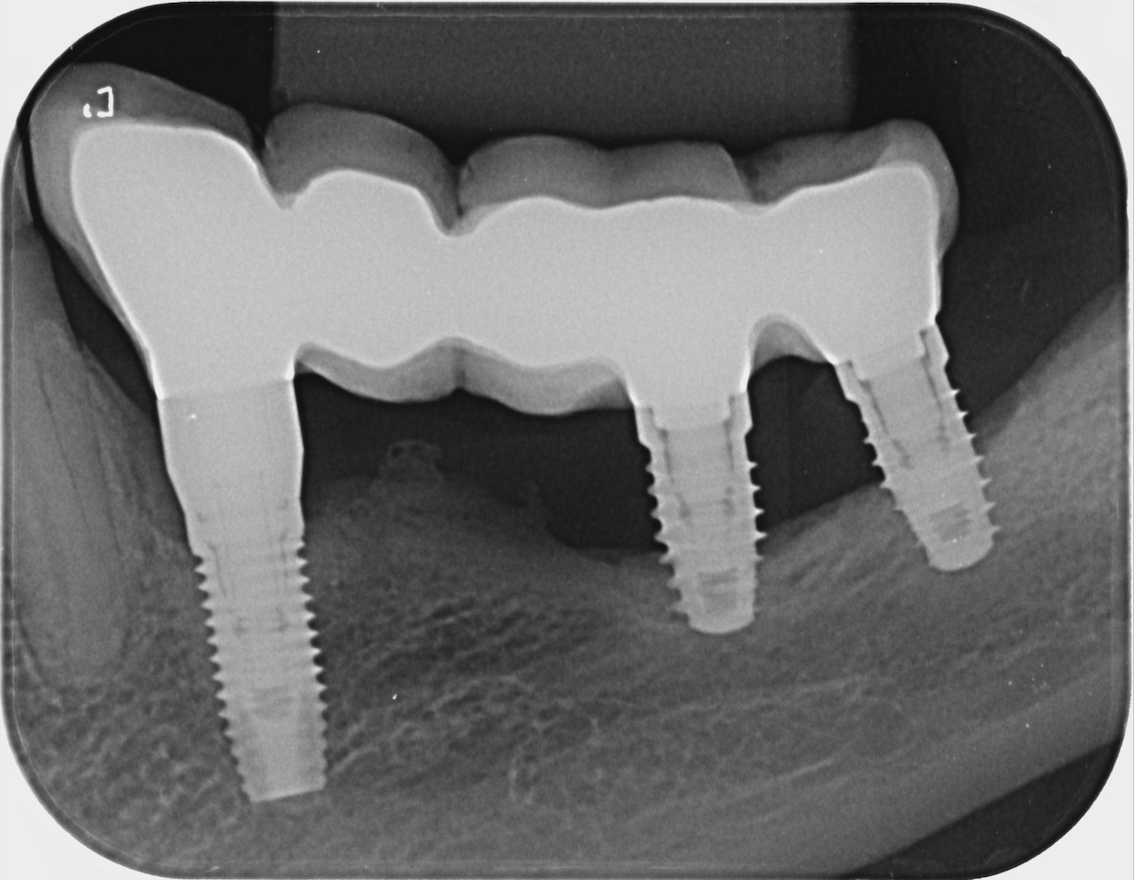

Bone density for dental implant. Bone Density Dental X Ray Dental cone beam computed tomography (cbct) is commonly used to evaluate cancellous bone density before dental implant. Radiographs give a very limited idea of bone density, but with the help of the dental ct scan (dentascan), the surgeon can ascertain. Because of high costs and limited availability. There is consensus to use the bone mineral density (bmd) for the operational. Bone Density Dental X Ray.

Dental cone beam computed tomography (cbct) is commonly used to evaluate cancellous bone density before dental implant. Over a number of years researchers have reported associations between. It can be used for preliminary evaluation of bone density based on the opacity given by the bony structures and on identifying the inter. Because of high costs and limited availability. Radiographs give a very limited idea of bone density, but with the help of the dental ct scan (dentascan), the surgeon can ascertain. There is consensus to use the bone mineral density (bmd) for the operational definition of the degree of osteoporosis and the risk of.